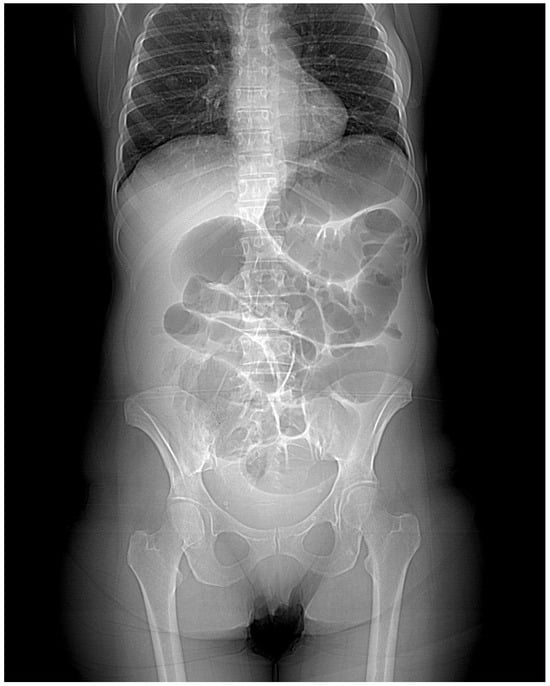

The first patient, a 48-year-old woman, came to the general Emergency Room in March 2023. She had been experiencing abdominal pain, distention, and intestinal obstruction a few days before her visit. Importantly, she exhibited no signs of fever and had no notable medical history. A CT scan showed an enlarged right adnex with multiple fluid-filled cysts (Figure 1). The left side of the uterus appeared thickened and was in continuity with the left bladder wall (Figure 2). Moreover, the colonic wall displayed thickening and hyperemia. The abdominopelvic area contained heterogeneous material with fluid pockets and signs of peritoneal fluid effusion. Consequently, the patient was referred for a gynecological evaluation. Clinical findings indicated abdominal distension accompanied by pain upon palpation. A bimanual examination uncovered indeterminate solid tissue. The ultrasound revealed a thin, linear endometrium and an enlarged right ovary, while the left ovary was significantly adhered to the sigmoid colon. Laboratory results showed an elevated white blood cell count (15.02 × 103/µL) and a higher C-reactive protein level (CRP 40.49 mg/L). Due to the high suspicion of gynecological malignancy, the patient underwent surgical procedures including laparotomic hysterectomy, bilateral tubo-oophorectomy, sigmoid resection with ileostomy, removal of the round ligament, omentectomy, appendectomy, and peritoneal biopsies. Intraoperative observations noted substantial adhesions involving the uterus, ovaries, and the sigmoid–rectal tract, along with mild ascitic effusion. An intraoperative histological assessment identified Actinomyces colonies. Despite this, the extensive disease burden suggested that demolitive surgery was warranted. Histological examination of the specimen diagnosed pelvic inflammatory disease featuring a tubo-ovarian abscess, revealing necrotic tissue with inflammatory characteristics, significant inflammation, and Actinomyces colonies mainly in the round ligament and right ovary. As a complication, the patient required a bilateral pyelostomy because of a left ureteral fistula linked to pelvic effusion stemming from past inflammation and vesicoureteral reflux. Nine months later, she underwent ano–rectal fistula repair. She received three months of antibiotic therapy with Amoxicillin and Doxycycline, followed by an additional eleven months of Amoxicillin, depending on complications after surgery. Fourteen months post-initial procedure, an X-ray with barium enema/CT scan was performed, indicating significant remission of complications. Currently, she is asymptomatic and continues to attend follow-up appointments monitoring.

Considering the imaging findings, the pelvic masses observed in both cases presented characteristics indicative of a potential malignancy. The masses were primarily associated with adnexal structures, exhibiting either cystic or solid contents and forming adhesions with adjacent anatomical entities. Although the ultrasound examination may have yielded nonspecific results, the CT scan also displayed images suggestive of gynecological malignancy. It would be improbable to suspect a benign pathology based solely on clinical examination and imaging findings, corroborating the existing literature.